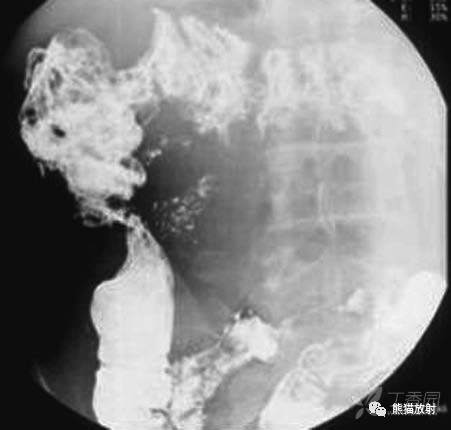

结核性腹膜炎

TUBERCULOUS PERITONITIS

结核性腹膜炎。大网膜增厚,腹水,肠袢外移

结核性腹膜炎。小肠轻度扩张并肠环间距增加

结核性腹膜炎。大网膜增厚,腹水

结核性腹膜炎累及肠系膜,肠管固定,粘膜增厚。